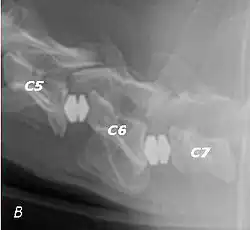

Doberman C6-C7 and C5-C6 traction responsive myelopathy B

T2 weighted MRI in neutral (A) and linear traction (B) of a seven-year-old Doberman with a two-year history of cervical pain treated with NSAIDs and presented acutely tetraplegic: A C6-C7 and C5-C6 traction responsive myelopathy are evident on MRI. The spinal-cord hyperintensity seen at the C5-C6 is suggestive of chronic lesion and most likely responsible for the chronic history of cervical pain, while the C5-C6 lesion was most likely responsible for the acute tetraplegia.